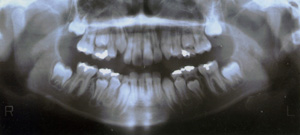

又、最近主流の考え方として、アーリートリートメントといって、永久歯の生えそろう永久歯列期が完成する前段階から医学的な介入を行い歯並びや咬み合わせが正しくなるよう管理・指導していくことで、将来大掛かりな矯正治療を避けられるようになりました。

ムーシールド(小児矯正)

幼少期の反対咬合(受け口)は自然治療が見込まれますが、2歳で反対咬合だったお子様の50%は自然治癒する一方で、3歳になると、自然治癒率は6%まで低下すると言われています。つまり、反対咬合は3歳より治療適応となります。従来の矯正治療では低年齢児に対応出来る治療法はごくわずかに過ぎず、大人の歯に全部生え変わったら矯正治療で治しましょうと言って、その時期まで何もしないという考え方が主流でした。

現在では、アーリートリートメントといって、早期治療によって将来予測される症状を少しでも軽くし、良い方向へ修正して行く、という考え方が確立されています。

例えば、叢生(でこぼこした歯並びの乱杭歯)の矯正治療の場合はある程度永久歯が生えそろう10歳程度まで様子を観察しますが、反対咬合の場合は放置しておくとかえって悪い状態になってしまうことが予測されるため、その事実を御説明し、早めの対処をお薦めしております。特に反対咬合は大人になると大きな審美障害を来たし、それからでは大掛かりな治療(下顎の骨を切る手術)をしなければ改善は難しくなってしまいます。

ムーシールドは就寝中にマウスピース型の矯正装置をくわえるだけという簡便さで、幼いお子様に対しても非常に少ない負担で応用出来ます。上口唇圧を排除し、口唇圧のバランスを整え、低位舌を改善し、逆被蓋の改善を促します。使用期間は1年間で、就寝時に装着させるか、日中2時間以上装着させて下さい。その後、定期的な経過観察が必要です。

適応年齢はムーシールドSサイズが乳歯列期のお子様(3~5歳)、ムーシールドMサイズが混合歯列期のお子様(6~11歳)となっており極端な反対咬合のお子様(反対咬合のうち5%程度)は、その後本格的な矯正治療が必要な症例もございますので、御了承下さい。